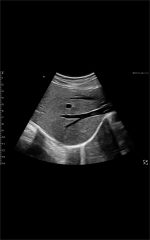

Galería de demostración

|